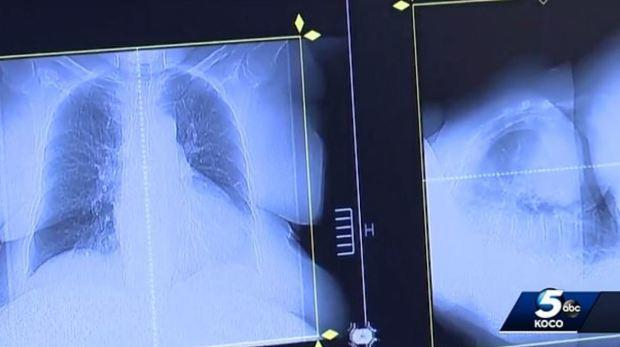

两次PET扫描结果,可以看出2017年1月(左)与2018年5月(右)的两次扫描结果差别巨大。ABC5台